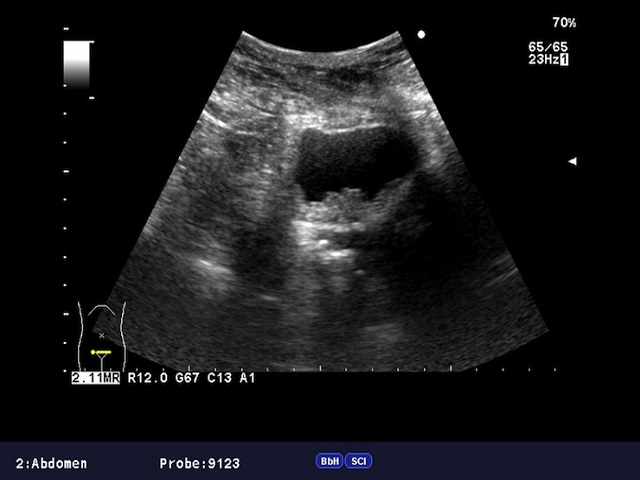

Чтобы ответить на этот вопрос, необходимо разобраться в принципе работы ультразвукового аппарата. Разные ткани обладают различной плотностью, что влияет на их способность пропускать ультразвук. Это и является основой функционирования УЗИ. При проведении исследования на экране формируется изображение, где ткани с различной проницаемостью отображаются в разных цветах. Участки с низкой проницаемостью обозначаются более светлыми оттенками.

При раке, когда происходит разрастание эндометрия и формируется опухоль, изменяется ультразвуковая проницаемость соответствующей ткани. Поэтому опухоль может быть визуализирована на УЗИ. Эффективность этого метода достаточно высока на средних и поздних стадиях заболевания. Однако на ранних этапах, когда изменения незначительны, признаки онкологического процесса могут быть незаметны. На более поздних стадиях информативность УЗИ достигает 80-90%.

Хотя основным диагностическим признаком остается проницаемость тканей, то есть, контрастность участков изображения, можно рак эндометрия на УЗИ диагностировать и иными способами. Например, в ходе такого исследования можно оценить контуры органа и его полости, состояние полости. Также важную роль играет размер матки, так как при наличии опухоли он, обычно, увеличивается. Если полость расширена, контуры эндометрия и эхогенность изменены, то это говорит в пользу рака.